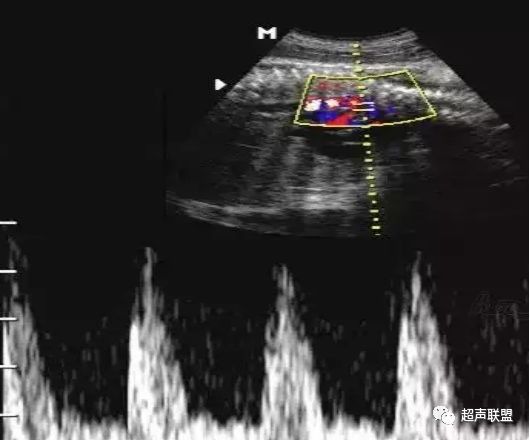

图2 脐动脉舒张期血流消失或反向